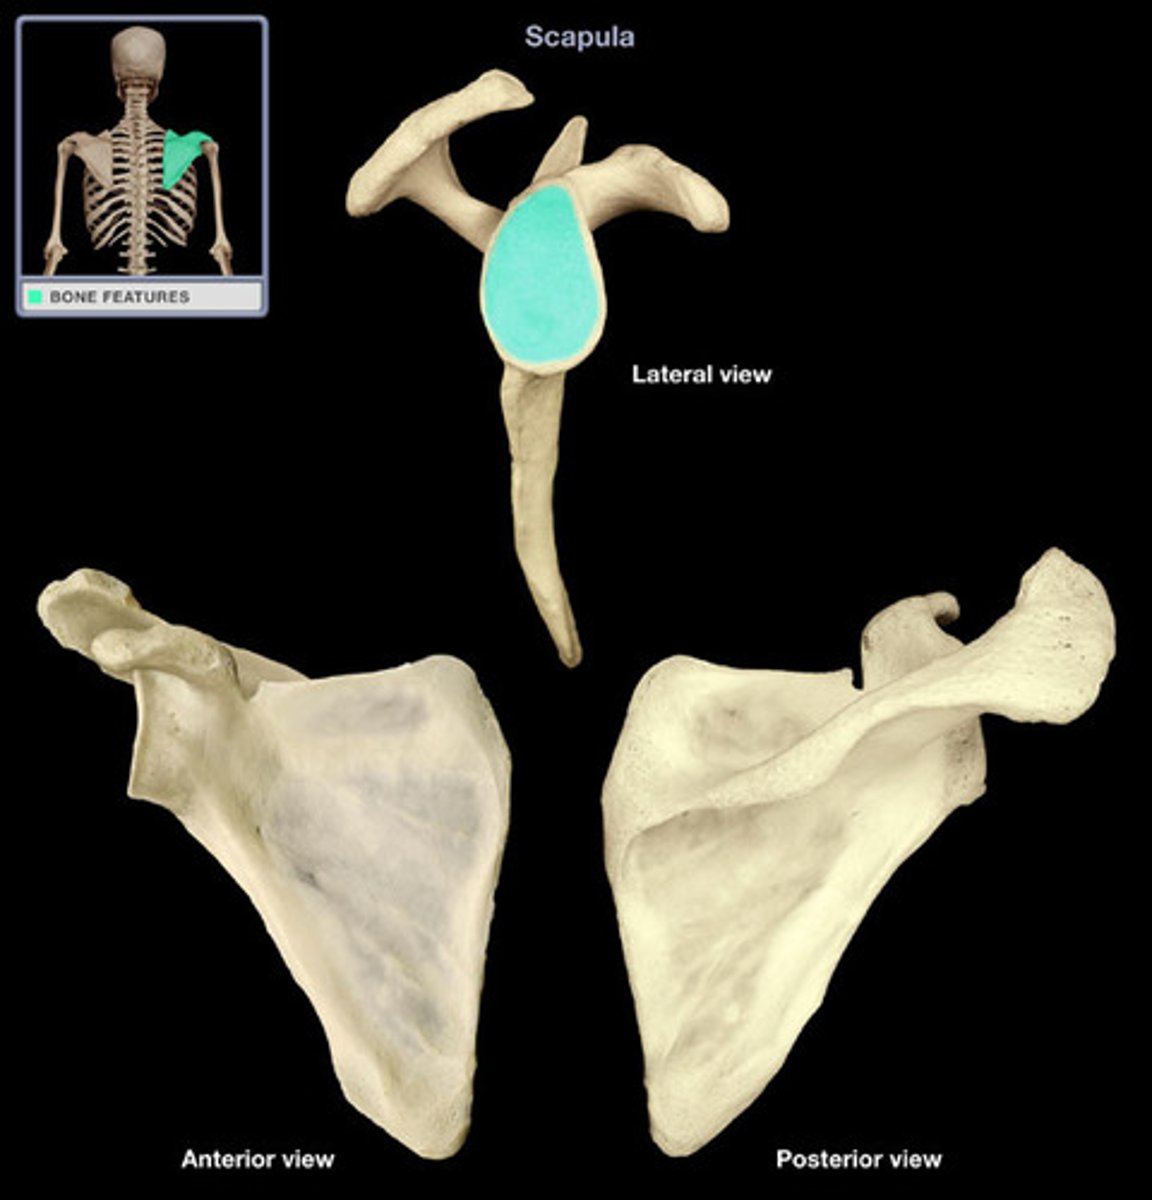

Scapula

shoulder blade

Acromion process

extension of the scapula, which forms the high point of the shoulder

Coracoid process

process above the glenoid cavity that permits muscle attachment

Glenoid fossa

The part of the scapula that joins with the humeral head to form the glenohumeral joint.